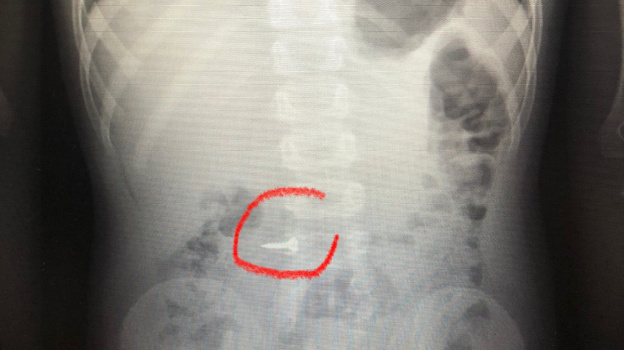

Врачи областной детской клинической больницы №2 в Воронеже поделились рентгеновскими снимками детей, которые проглотили шуруп, гайку или другие инородные предметы. Фото опубликовали в соцсети учреждения в понедельник, 19 июня. Медики отметили, что количество обращений в приемное отделение с жалобой на возможное проглатывание ребенком инородного тела не снижается.